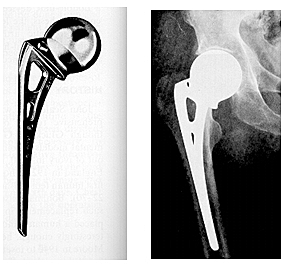

• Reemplazo de cadera, diseño endoprotesis Thompson

Reemplazo de cadera, diseño endoprotesis Thompson

Prótesis metálicas con vástagos medulares para la fijación esquelética. Desarrollados en Estados Unidos por Fred Thompson. Para fijación a presión dentro del canal medular.